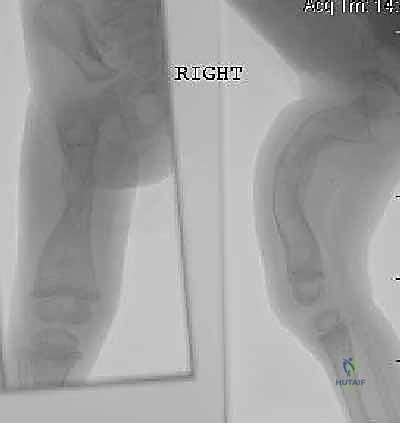

الخطوة الأولى: التخطيط الجراحي الدقيق (Pre-operative Planning)

قبل العملية، يقوم الدكتور هطيف بإجراء دراسة شاملة لصور الأشعة السينية (X-rays) المأخوذة بدقة، لحساب زوايا التقوس بدقة متناهية، وتحديد نقاط بضع العظم (أماكن القص)، واختيار الحجم والطول المناسبين للمسمار التلسكوبي.

- يتم إجراء أشعة سينية للتأكد من بدء تكوّن الدشبذ العظمي (Callus) حول مناطق القص.

كان عمار يعاني من النوع الثالث من تخلّق العظم الناقص، مع تقوس شديد في عظمي الفخذين (بشكل حرف O) منعه من المشي تماماً، وجعله حبيس الكرسي المتحرك، مع تاريخ من 8 كسور سابقة. تم إجراء عملية بضع العظم المتعدد عبر الجلد وتركيب مسامير فاسييه-دوفال التلسكوبية في كلتا الساقين في جلسة جراحية واحدة بواسطة الدكتور هطيف. اليوم، وبعد 6 أشهر من الجراحة، يمشي عمار مستقلاً لأول مرة في حياته، ولم يتعرض لأي كسر جديد.

عانت رؤى من كسور متكررة في عظم القصبة (الساق) بمجرد محاولتها الجري. أظهرت الأشعة هشاشة شديدة وتقوساً أمامياً. بعد استشارة الأستاذ الدكتور محمد هطيف، تقرر إجراء التدخل الجراحي المحدود. تم تصحيح التقوس بنجاح باهر، وبفضل المسمار التلسكوبي الذي ينمو معها، عادت رؤى للعب مع أقرانها بثقة وأمان.